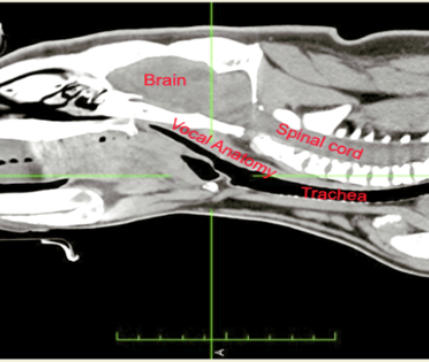

In the more conventionl 2d CAT scan image below, you can see a section through vocal cord anatomy of a male wombat know as KIAL